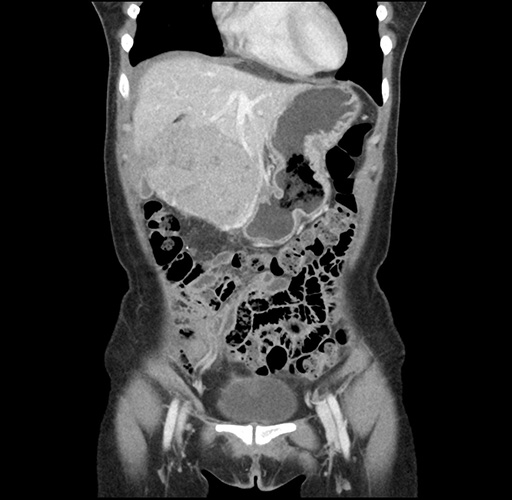

Imaging Analysis

Look through the patient's CT scan to identify any areas of concern for the necessary procedure.

Based on your CT findings, which issue(s) would give reason for "planned slowing down moment(s)" in this case?